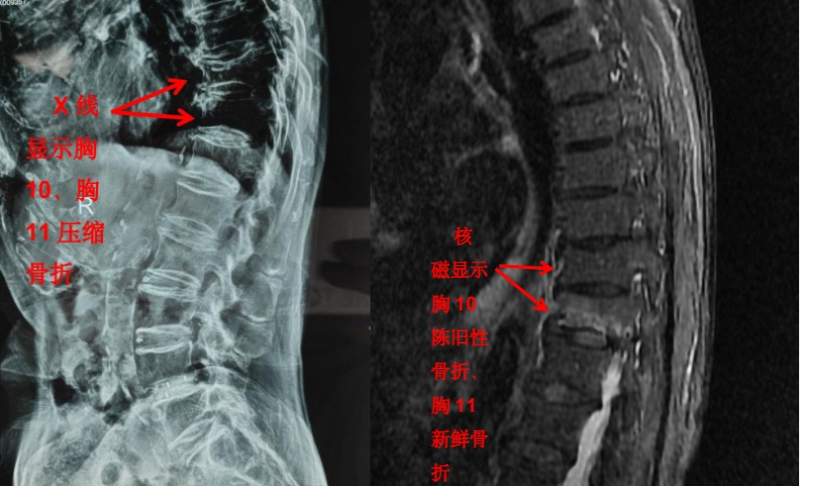

但是對(duì)于大部分軟組織病變?nèi)缱甸g盤(pán)、椎管內(nèi)神經(jīng)、有沒(méi)有占位性病變等卻無(wú)能為力。如果患者有壓縮骨折,X 光片也無(wú)法判斷是新鮮骨折還是陳舊骨折,這樣也就無(wú)法定制下一步診療計(jì)劃。

隨著科技進(jìn)步及醫(yī)學(xué)的發(fā)展,核磁已經(jīng)是脊柱外科不可或缺的檢查手段。對(duì)脊柱、韌帶、椎間盤(pán)、椎管內(nèi)神經(jīng)及椎旁組織顯影都優(yōu)于 CT,通過(guò)腰椎核磁我們可以直觀地看到椎間盤(pán)突出的程度、神經(jīng)受壓的程度,以及壓縮骨折的新鮮程度。

核磁雖然顯像更全面,但都是層掃,直觀整體的信息欠缺,X 光片雖然內(nèi)容少,但可以顯示出脊柱整體的影像。幾種檢查互相補(bǔ)充,可以讓疾病診斷更加明確。

前面提到的腰椎壓縮骨折,X 光片可以看出楔形變,但無(wú)法判斷新鮮骨折還是陳舊骨折,進(jìn)一步完善腰椎 MRI 才能明確診斷,做出下一步治療計(jì)劃。